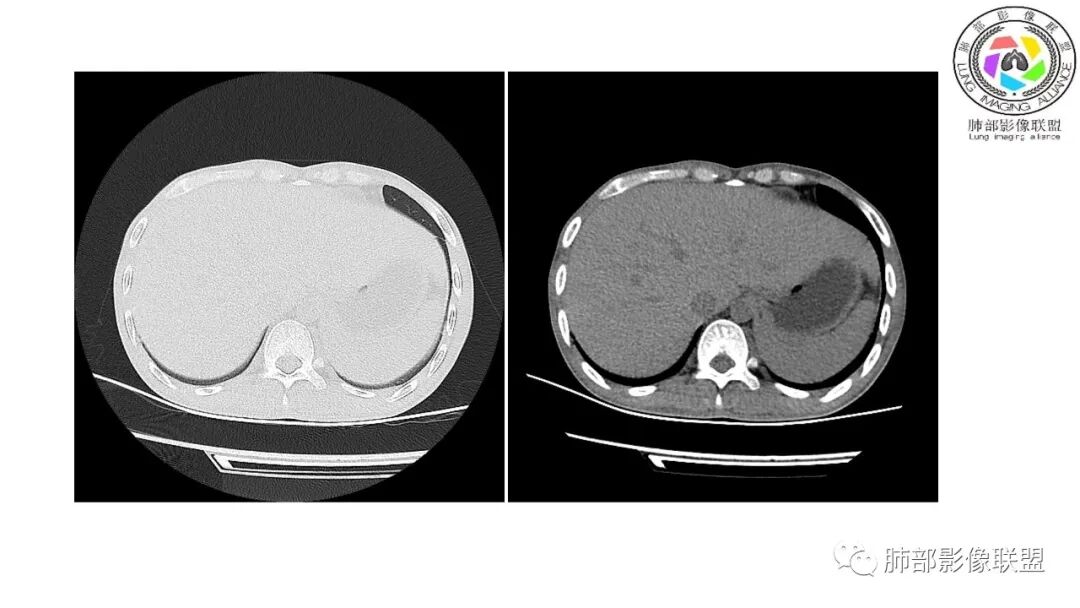

以下为2021-7-15日上腹部CT

影像与临床:1.青年男性,HlV阳性,颜面部皮疹(未提供皮疹图像)、发热(高热),实验室CRP、PCT高,T-Spot阴性。2.右肺下叶空洞结节,壁厚不均,边界清楚,其内线状影,未见液平及钙化,未见卫星灶,纵隔淋巴结增大,双侧腋窝见增大淋巴结。心腔内低密度提示贫血可能。肝脾影增大,未见结节影及块影。腹膜后见多发增大淋巴结。